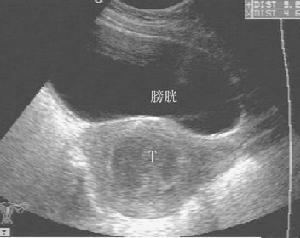

目前国内B超检查较为普遍。鉴别肌瘤,准确率可达93.1%,它可显示子宫增大,形状不规则;肌瘤数目、部位、大小及肌瘤内是否均匀或液化囊变等;以及周围有否压迫其他脏器等表现。由于肌瘤结节中肿瘤细胞单位体积内细胞密集,结缔组织支架结构的含量及肿瘤、细胞排列不同,而使肌瘤结节于扫描时表现为弱回声,等回声和强回声3种基本改变。弱回声型是细胞密度大,弹力纤维含量多,细胞巢状排列为主,血管相对丰富。强回声型,胶原纤维含量较多,肿瘤细胞以束状排列为主。等回声型介于两者之间。后壁肌瘤,有时显示不清。肌瘤愈硬衰减表现愈重,良性衰减比恶性明显。肌瘤变性时,声学穿透性增强。恶变时坏死区增大,其内回声紊乱。故B超检查既有助于诊断肌瘤,区别肌瘤是否变性或有否恶性变提供参考,又有助于卵巢肿瘤或其他盆腔肿块的鉴别。